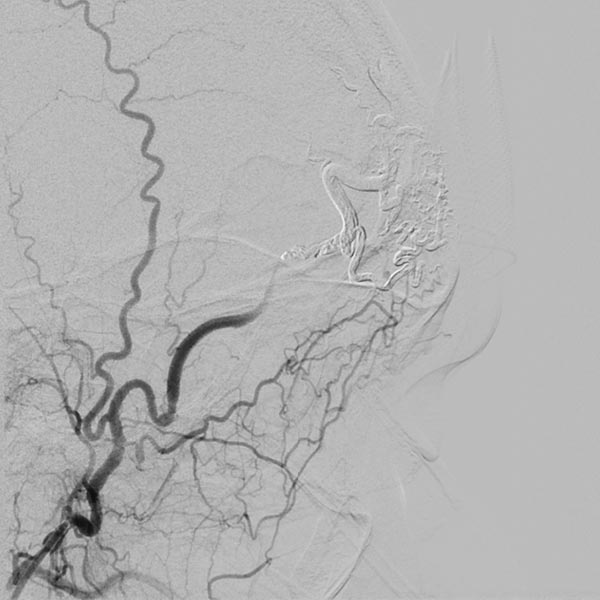

Die Abschlussangiographie nach Injektion in die rechte Arteria carotis externa zeigt den kompletten Verschluss des Nidus der arteriovenösen Malformation. Durch die Subtraktionsdarstellung erscheint der Cast hier weiß.

Die Bilder der initialen Angiographie und des Ausgusses der AVM mit dem Embolisat demonstrieren die Vollständigkeit des Verschlusses.